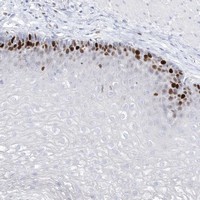

- Immunohistochemical staining of human esophagus with TMCO6 polyclonal antibody (Cat # PAB23117) shows strong nuclear positivity in squamous epithelial cells at 1:50-1:200 dilution.

- Immunohistochemistry (Formalin/PFA-fixed paraffin-embedded sections)